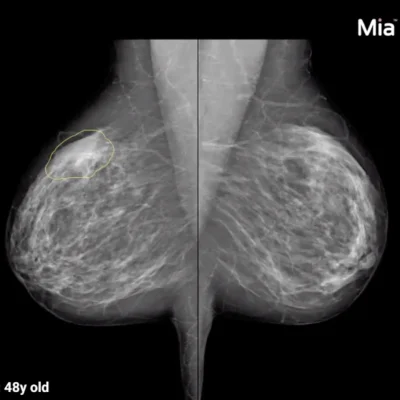

Mia or Mammography Intelligent Assessment, is designed to support breast radiologists in making the critical decision to recall women for further testing based on their mammography screening.

Mia is the first solution of its kind to receive the CE (European regulatory clearance) mark for use as an AI-enabled independent reader for the detection of breast cancer. Through rigorous clinical studies and testing, Mia has learnt to read mammograms to the same level of detail as a consulting radiologist.

In double-reading mammography workflows where scans are reviewed by two radiologists, Mia can be deployed independently alongside a single human reader. This delivers the quality improvements needed to ensure the sustainability of breast screening services and frees up clinicians to spend more time with patients. Mia can also be deployed as a concurrent reader or in double reader triage.